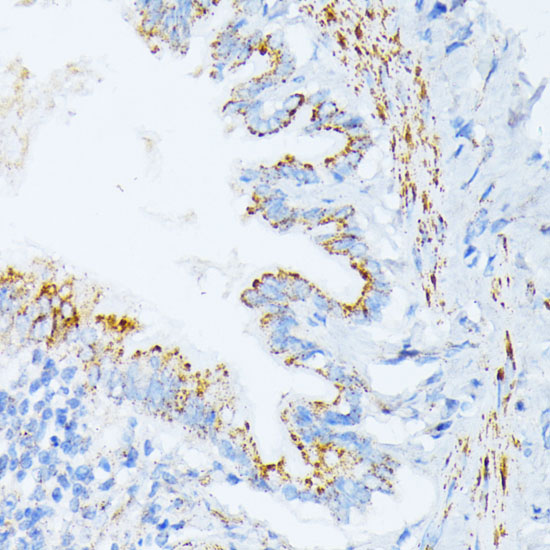

Immunohistochemistry of paraffin-embedded rat lung using IL3RA at dilution of 1:100 (40x lens).